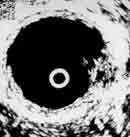

Эндовезикальное сканирование позволяет дифференцировать все слои мочевого пузыря (Рис. 1). Между мышечной стенкой и слизистой оболочкой визуализируется гипоэхогенная подслизистая соединительная ткань. При стадии рака мочевого пузыря Та (инвазия в пределах слизистой) создается впечатление, что опухоль отделена от мышечной стенки мочевого пузыря, то есть подслизистый слой остается неизмененным (Рис. 2), также хорошо визуализируются устья мочеточников. При распространении инвазии субэпителиальной соединительной ткани (стадия Т1) опухоль уже непосредственно прилежит к мышечному слою, но не инвазирует последний (Рис. 3).

Увеличить

Рис. 2. Цистэндосонограмма. Рак мочевого пузыря стадия Та.

1 - опухоль,

2 - устья мочеточников.